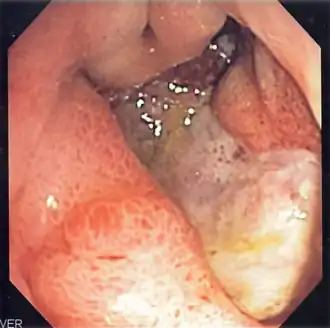

La esofagogastroduodenoscopia (EGD), también llamada endoscopia gastrointestinal alta, panendoscopia oral o simplemente gastroscopia (en algunos países hispanohablantes, las palabras terminadas en -scopia se usan con acento:-scopía) es un examen médico que visualiza el esófago, el estómago y el duodeno. Para su realización se utiliza un endoscopio, unos tubos flexibles cuya cabeza es móvil y controlada por el operador, en cuya punta tienen una cámara de video y una luz que ilumina el órgano examinado. La imagen es transmitida a un monitor en donde se pueden identificar lesiones como úlceras, erosiones y neoplasias de los órganos examinados. Durante el procedimiento también se pueden obtener muestras de tejido para realizar biopsias.

El examen también se puede emplear para obtener una muestra de tejido para realizar una biopsia. En una EGD, normalmente el esófago, el estómago y el duodeno deben estar lisos y de color carnoso. No debe haber sangrado, neoplasias, úlceras ni inflamación. Los resultados anormales pueden mostrar divertículos (bolsas anormales en el revestimiento de los intestinos), anillos esofágicos, esofagitis, estrechez de esófago, varices esofágicas, hernia de hiato, masas gástricas, inflamación del estómago y el duodeno, síndrome de Mallory-Weiss (desgarro), oclusión del tracto digestivo, tumores y úlceras (agudas o crónicas) en cualquiera de los tres órganos.

El endoscopista, con el paciente tumbado sobre su costado izquierdo, introduce el endoscopio por la boca en el esófago y luego procede a entrar al intestino delgado en su primera parte llamada duodeno. Desde allí se regresa examinando cada parte con detenimiento para encontrar lesiones. Si se encuentra una lesión se puede tomar una biopsia por el canal de trabajo del endoscopio.